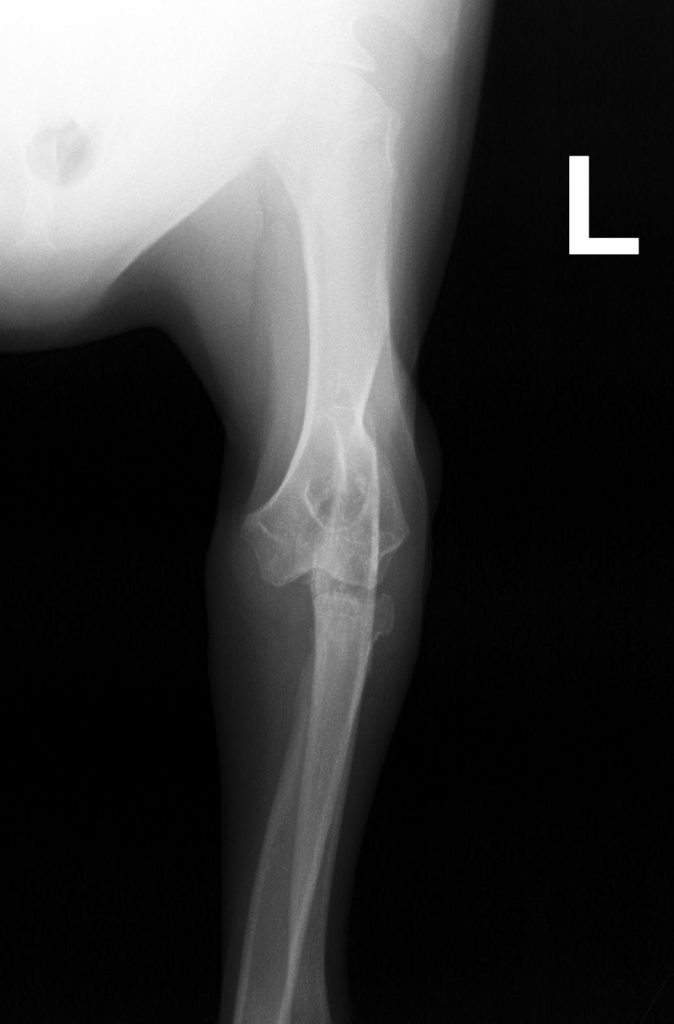

Dysplazje stawu łokciowego

Dysplazje łokciowe u psów to zespół wad rozwojowych stawu łokciowego, które prowadzą do nieprawidłowego obciążenia chrząstki i kości, a w konsekwencji – do rozwoju wczesnej choroby zwyrodnieniowej (artrozy).

Pod pojęciem „dysplazja łokciowa” kryją się cztery główne nieprawidłowości:

- UAP – nieprzyrośnięty wyrostek łokciowy dodatkowy,

- FCP – fragmentacja wyrostka dziobiastego przyśrodkowego,

- OCD – osteochondroza chrząstki bloczka kości ramiennej,

- INC – inkongruencja stawu łokciowego (niedopasowanie powierzchni kości).

Wszystkie te zmiany mogą występować pojedynczo lub łącznie. Choroba rozwija się głównie u psów ras dużych i szybko rosnących (np. owczarki niemieckie, labradory, golden retrievery, rottweilery).

Diagnostyka

- Wywiad i badanie kliniczne – ocena kulawizny, bolesności i zakresu ruchu,

- RTG (rentgen) – podstawowe badanie, choć ze względu na złożoność stawu łokciowego, nie zawsze pozwala wykryć wszystkie zmiany

- TK (tomografia komputerowa) – bardzo dokładna ocena struktur kostnych, szczególnie przy podejrzeniu FCP

- Artroskopia – metoda inwazyjna, ale umożliwia jednocześnie diagnostykę i leczenie (usunięcie fragmentów chrząstki/kostnych).